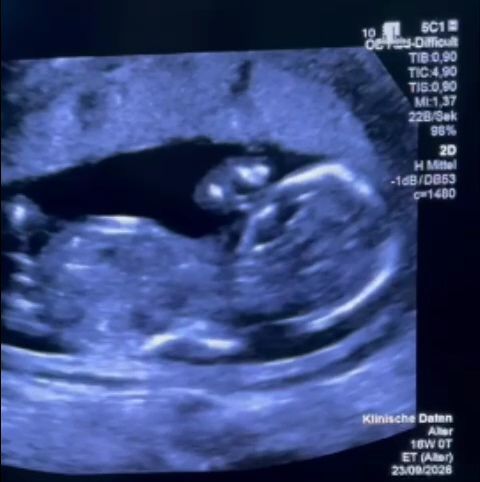

În cele din urmă, familia a plecat în Germania, unde a primit îngrijiri medicale urgente. Profesorul Kohl a montat cu succes un shunt vezico-amniotic, intervenție care a salvat viața fătului. Medicul german a menționat într-o postare pe Instagram „o consiliere extrem de slabă” primită de gravida în România.

Profesorul Kohl a subliniat că rezultatele tratamentelor pentru această afecțiune sunt publice și disponibile gratuit. Intervenția medicală a avut loc în ziua de Paște catolic și a fost un succes.